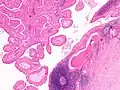

The appearance of this tumor under the microscope is unique. There are cystic spaces surrounded by two uniform rows of oncocytes, which are epithelial cells with abundant, granular, eosinophilic cytoplasm.[7] The cystic spaces have epithelium referred to as papillary infoldings that protrude into them. Additionally, the epithelium has lymphoid stroma with germinal center formation.